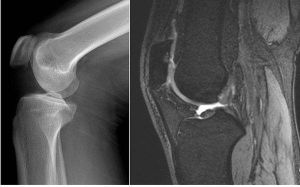

A型:股骨頭及髖臼正常,股骨短縮畸形,早期X線片顯示股骨頸缺如。隨年齡增長軟骨性股骨頸有可能骨化自愈,也可形成假關節。X線片顯示有嚴重的髖內翻及明顯的肢體短縮畸形。

B型:與A型相似,髖臼及股骨頭均存在,股骨近端與股骨頭之間無骨性連線,假關節形成。